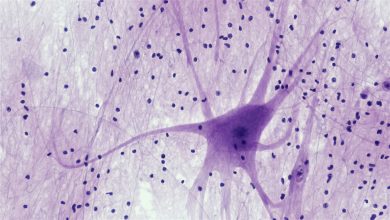

Insultos genotóxicos geram resultados divergentes em células-tronco de melanócitos (McSCs). Sob exposição à genotoxina citotóxica, como a irradiação de raios X, a auto-renovação do McSC é prejudicada, levando à depleção e ao envelhecimento dos cabelos. Na homeostase, as McSCs mantêm a auto-renovação e o equilíbrio pigmentar. As genotoxinas cancerígenas, no entanto, promovem a sinalização KIT e alteram o metabolismo do ácido araquidônico, dando origem a clones fundadores do melanoma e à progressão para o melanoma. Crédito: Emi K. Nishimura / Universidade de Tóquio, Japão

As células-tronco de melanócitos (McSCs) são células-tronco residentes nos tecidos que servem como fonte de melanócitos maduros, as células produtoras de pigmento responsáveis pela coloração do cabelo e da pele. Nos mamíferos, essas células-tronco residem na região protuberante-sub-protuberante dos folículos capilares como melanoblastos imaturos, mantendo a pigmentação através da regeneração cíclica.